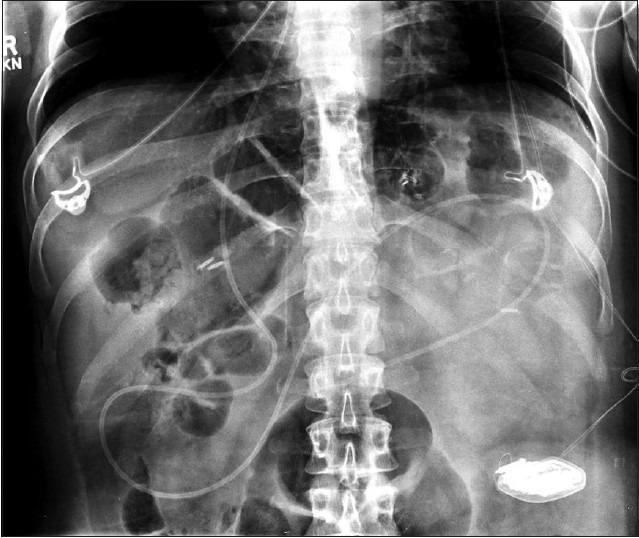

Ventriculo-peritoneal shunts (VPS) are commonly used in the treatment of various neurosurgical conditions, including hydrocephalus and pseudotumor cerebri. We report only the second case of vaginal extrusion of a VPS catheter in an adult, and the first case with a modern VPS silastic peritoneal catheter. A 45-year-old female with a history of VPS for pseudotumor cerebri, Behcet's syndrome, and hysterectomy presented to our institution with the chief complaint of tubing protruding from her vagina after urination. On gynecologic examination, the patient was found to have approximately 15 cm of VPS catheter protruding from her vaginal apex. A computed tomography scan of the abdomen and shunt X-ray series demonstrated no breaks in the tubing, but also confirmed the finding of the VPS catheter extruding through the vaginal cuff into the vagina. The patient had the VPS removed and an external ventricular drain was placed for temporary cerebrospinal fluid diversion. Ventricular catheter cultures were positive for diphtheroids. After an appropriate course of antibiotics, a contralateral ventriculo-pleural shunt was placed one week later. Although vary rare, vaginal extrusion can occur in adults, even with modern VPS catheters.

脑室-腹腔分流术(VPS)常用于治疗各种神经外科疾病,包括脑积水和假性脑瘤。我们报告的这例成人VPS导管经阴道脱出的病例为世界第二例,也是首例使用现代VPS硅橡胶腹腔导管的病例。一名45岁女性,有因假性脑瘤行VPS手术史、白塞病病史及子宫切除史,因排尿后有管道从阴道突出为主诉前来我院就诊。妇科检查发现,患者阴道顶端有大约15厘米长的VPS导管突出。腹部计算机断层扫描和分流X线系列检查显示管道无破损,但也证实了VPS导管经阴道断端突入阴道的情况。患者接受了VPS移除手术,并放置了外部脑室引流管进行临时脑脊液引流。脑室导管培养结果显示类白喉杆菌呈阳性。经过适当疗程的抗生素治疗后,一周后为患者进行了对侧脑室-胸膜分流术。尽管极为罕见,但即使使用现代VPS导管,成人也可能发生导管经阴道脱出的情况。